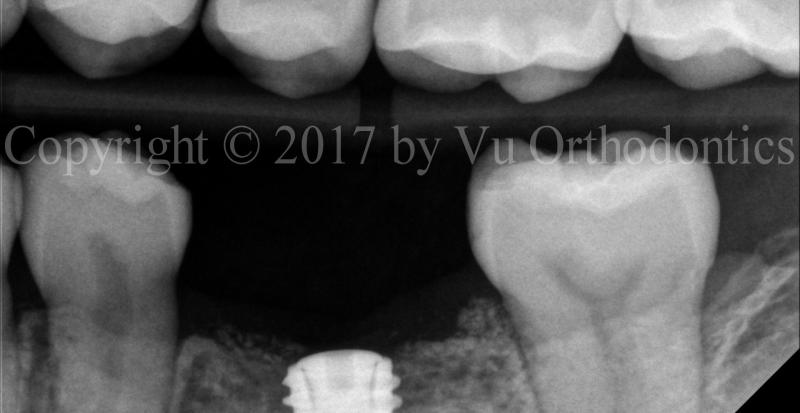

Multiple Implants

The following is an example of a multi-implant case, in which there is no room for error. Thus, a fully-guided system must be used for implant placement (Figs.7 & 8)

Fig. 7. A multi-implant case, fully guided (Sites #12, #13, and #14): planning

(a)

(b)

Fig. 8. A multi-implant case, using fully guided sytem, Sites #12, #13, and #14 -- implants and cover screws: (a) PA, and (b) BW

Note that for Site #14, the implant was tilted a bit to the mesial side (compared to the planning).